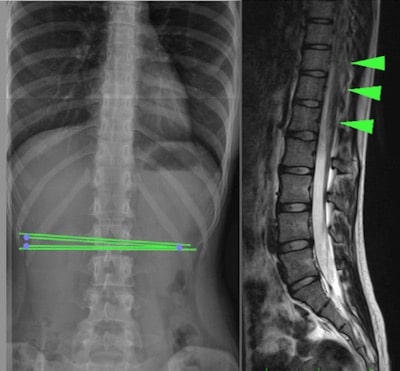

La medul·la ancorada oculta o “Occult Tethered Cord Syndrome” va associada a una espina bífida oculta, que és una malformació neuro-espinal que consisteix en el desenvolupament incomplet de la medul·la espinal (de predomini a la regió lumbar), que fixa la medul·la espinal i produeix lesions mecàniques per tracció, principalment medul·lars i vertebrals (Fig.1).

Per visualitzar-la i realitzar el diagnòstic són necessàries exploracions complementàries com la Ressonància Magnètica Nuclear (RMN) o la Tomografia Axial Computada (TAC) o una radiografia simple del nivell de la columna vertebral on es troba l’ancoratge.